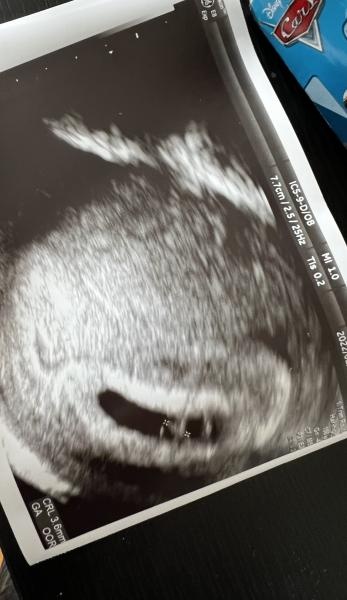

tidigt ultraljud var idag och allt såg bra, fick se hjärtat slå!

hon tyckte veckorna stämde bra och att jag har BF mitten av oktober Hjärta är idag ca 6+2

Vad roligt för dig :) hade oxå ultraljud idag :) men jag är 7+5 :)

Sellcarro skrev 2022-02-23 11:07:29 följande:

Såg det och så skönt att det såg bra ut för dig med! :)

var det stor skillnad på bilden jag visade? Tänkte att det händer så mkt på någon vecka bara